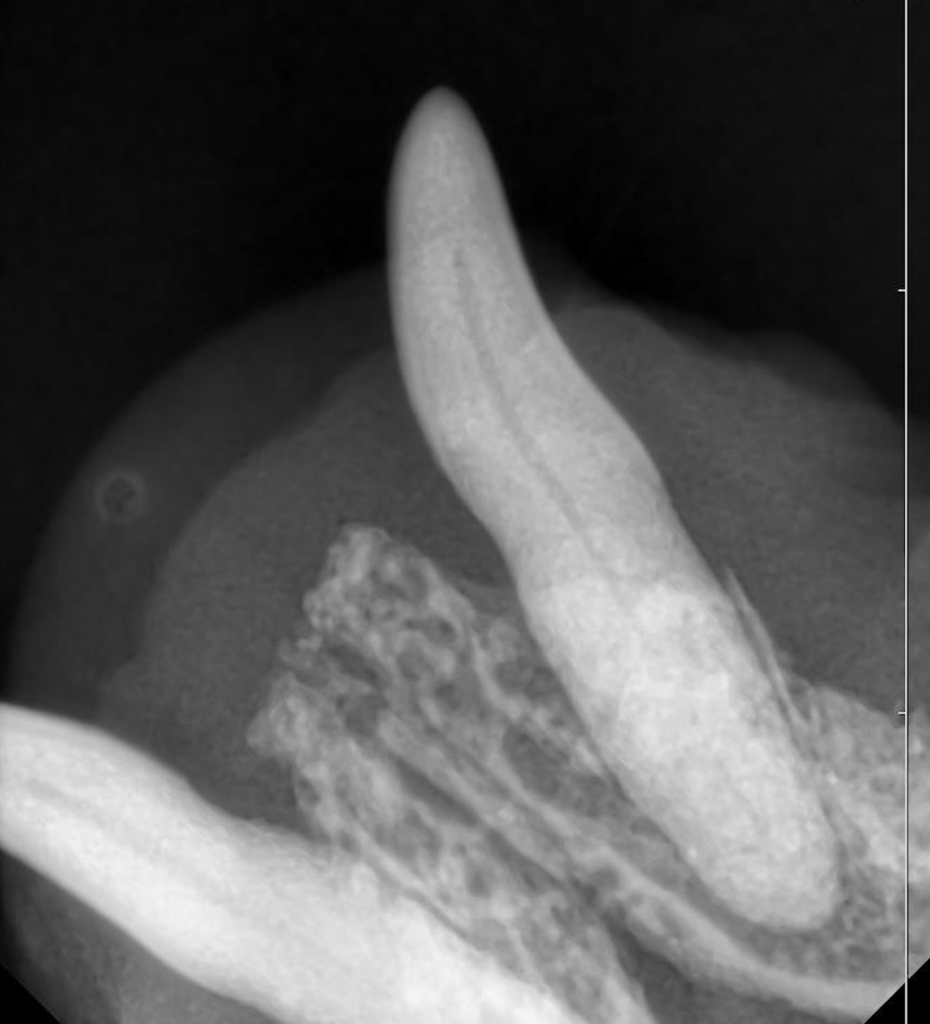

歯科レントゲンを撮ってみると歯を支える歯槽骨が融解しており、中程度歯周病と診断しました。

この歯は抜歯も適応になりますが、ある理由から歯を温存する治療を選択しました。

歯科レントゲン写真を見て分かるように、小型犬の下顎犬歯の歯根部は下顎骨に対して大きな割合を占めています。

そのため、抜歯処置自体によって骨折してしまうリスクや、抜歯後に抜歯窩を中心とした骨融解が起こることで骨折してしまうリスクがあります。

下顎骨の骨折は摂食など動物のQOLに大きく関わることが予測されますので、拡大鏡で歯根部を肉眼的に確認しながら超音波スケーラーで歯石を除去し、ダウンエピテーションを起こした歯肉を除去し温存しました。